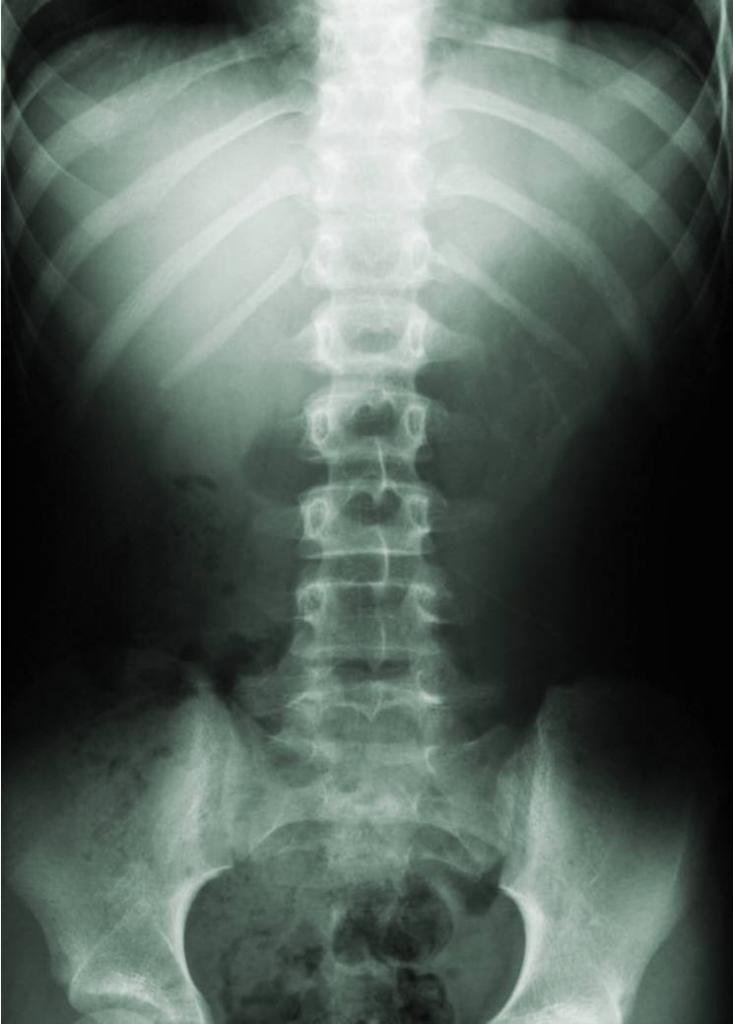

- Рентгенография. Определит место повреждения и его характер.

- КТ и МРТ более точно осветит картину происходящего, повреждение спинного мозга, позвонков и межпозвоночных дисков.